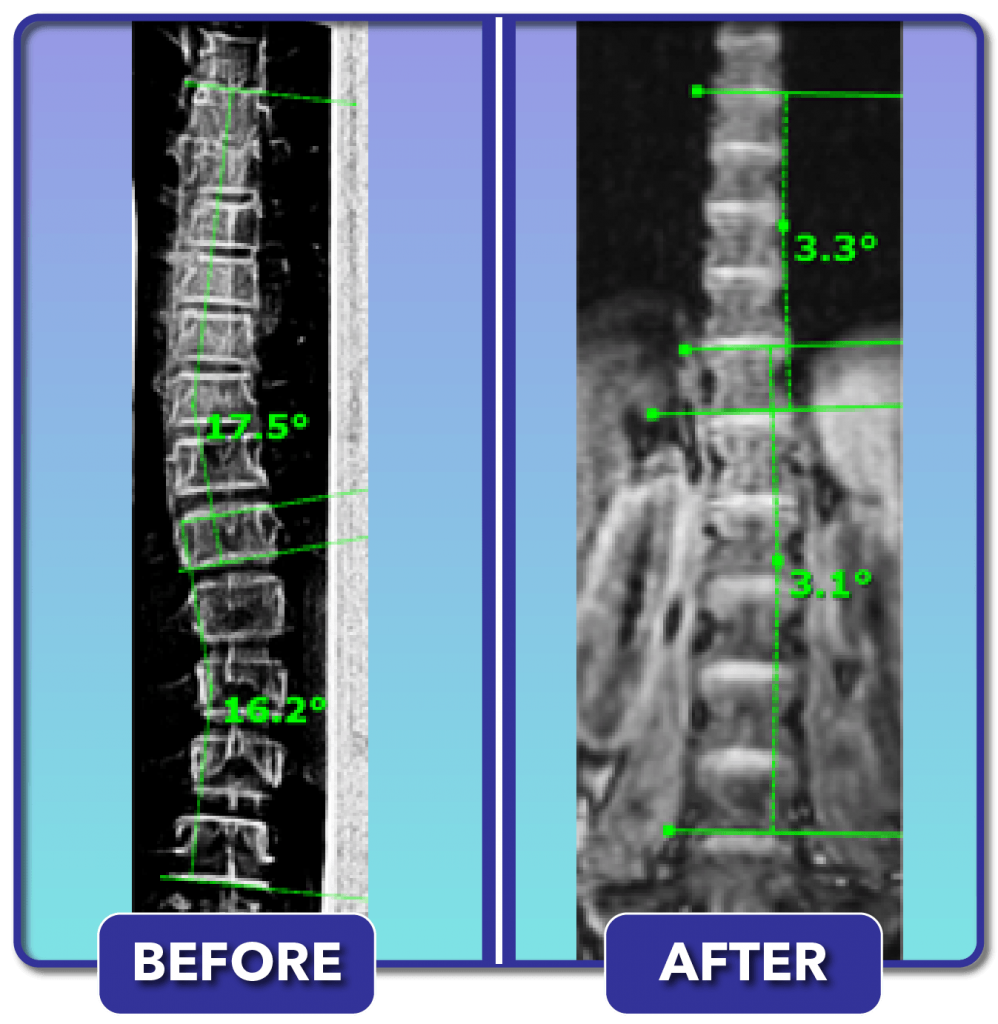

From scoliosiscarecenters.com

Scoliosis Before and After Treatment Results Scoliosis Care Centers Can You Run After Scoliosis Surgery Adults may need treatment to relieve pain, such as painkillers, spinal injections and, very occasionally, surgery. Patients should expect to follow plenty of dos and don'ts in the months after surgery that can help smooth their recovery, according to praveen kadimcherla, md, an. Depending on your age you. Can you exercise after scoliosis surgery? So that’s exactly what i do…!. Can You Run After Scoliosis Surgery.